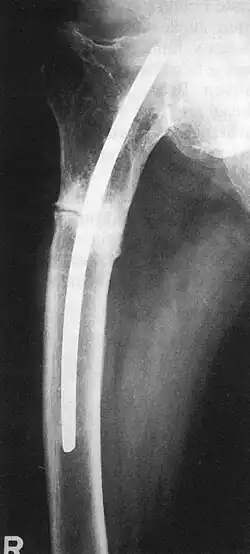

Küntscher befasste sich während dieser Zeit mit Bau und Funktion des Knochengewebes; in Experimenten für seine Habilitationsschrift stellte er erstmals den Kraftfluss in Röhrenknochen dar und erforschte die Bruchheilung und Kallusbildung. Mit Ernst Pohl als kongenialem „Handwerker“ inaugurierte Küntscher die Technik der intramedullären Bolzung zur Marknagelung, wobei er sich nach eigenem Bekunden an Vorarbeiten der (weithin unbekannt gebliebenen) Mediziner Oskar Müller-Meernach und Georg Schöne orientierte.1939 führte er erstmalig seine Technik der Marknagelung an einem menschlichen Schaftbruch des Oberschenkelknochens durch, nachdem ein Ingenieur aus großer Höhe in ein Trockendock einer Kieler Werft gestürzt war und sich dabei multiple Brüche der Beckens und der Beine zugezogen hatte.[7] Die „Innenschiene für Röhrenknochen“ ließ er sich kurz darauf, am 17. Dezember 1939, beim Reichspatentamt patentieren. Im März 1940 berichtet er dann erstmals auf dem 68. Chirurgenkongress in Berlin von seiner Technik, traf jedoch auf Ablehnung. Allein sein Chef Fischer sprang ihm so moderat wie entschieden bei, so dass die Technik in der Folge in Kiel weiter angewandt und in der Folge verfeinert wurde. Erst während des Zweiten Weltkrieges kam es zu einer schnellen Verbreitung seiner Technik. Auf dem Chirurgenkongress hatte Küntscher einen Marknagel mit V-förmigem Profil vorgestellt, dem im selben Jahr ein geschlitzter Marknagel mit kleeblattförmigem Querschnitt[8] folgte. In das Jahr 1940 fällt auch seine Erfindung des sog. Gammanagels, der – immer weiter vervollkommnet – bis heute zum Standardrepertoire bei der Behandlung hüftgelenksnaher („pertrochantärer“) Oberschenkelbrüche zählt.[7]